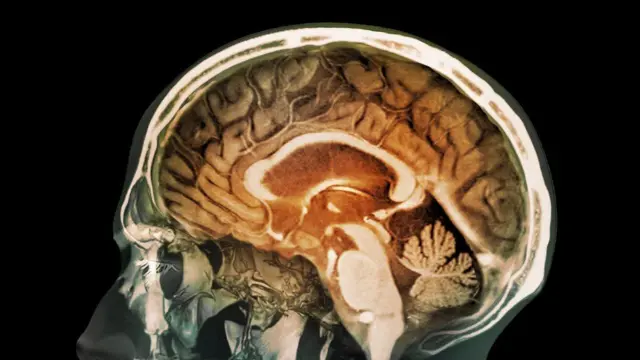

फोटो स्रोत, Science Photo Library

सिस्टीरकोसिस (Cystocercosis) हा एक प्रकारचा संसर्ग आहे जो परजीवी Taenia solium (T.solium) च्या अळ्यांमुळे होतो. त्यांना डुकराचे टेपवर्म असंही म्हणतात. या घटनेनंतर मेंदूमध्ये सिस्ट्स म्हणजेच गाठी तयार होऊ शकतात.

टेपवर्मच्या संपर्कात आलेली एखादी व्यक्ती टेपवर्म अंड्यांद्वारे संक्रमण करू शकते - या प्रक्रियेला ऑटोइन्फेक्शन असं म्हटलं जातं.

अमेरिकेतील सेंटर्स फॉर डिसीज कंट्रोल अँड प्रिव्हेन्शन (CDC) नुसार, जंत ऊतींमध्ये प्रवेश करतात आणि तेथून मेंदूमध्ये जातात आणि सिस्ट्स तयार करतात.

मेंदूमध्ये अशा सिस्टच्या उपस्थितीला न्यूरोसिस्टोसेरकोसिस (Neurocystocercosis) म्हणतात.